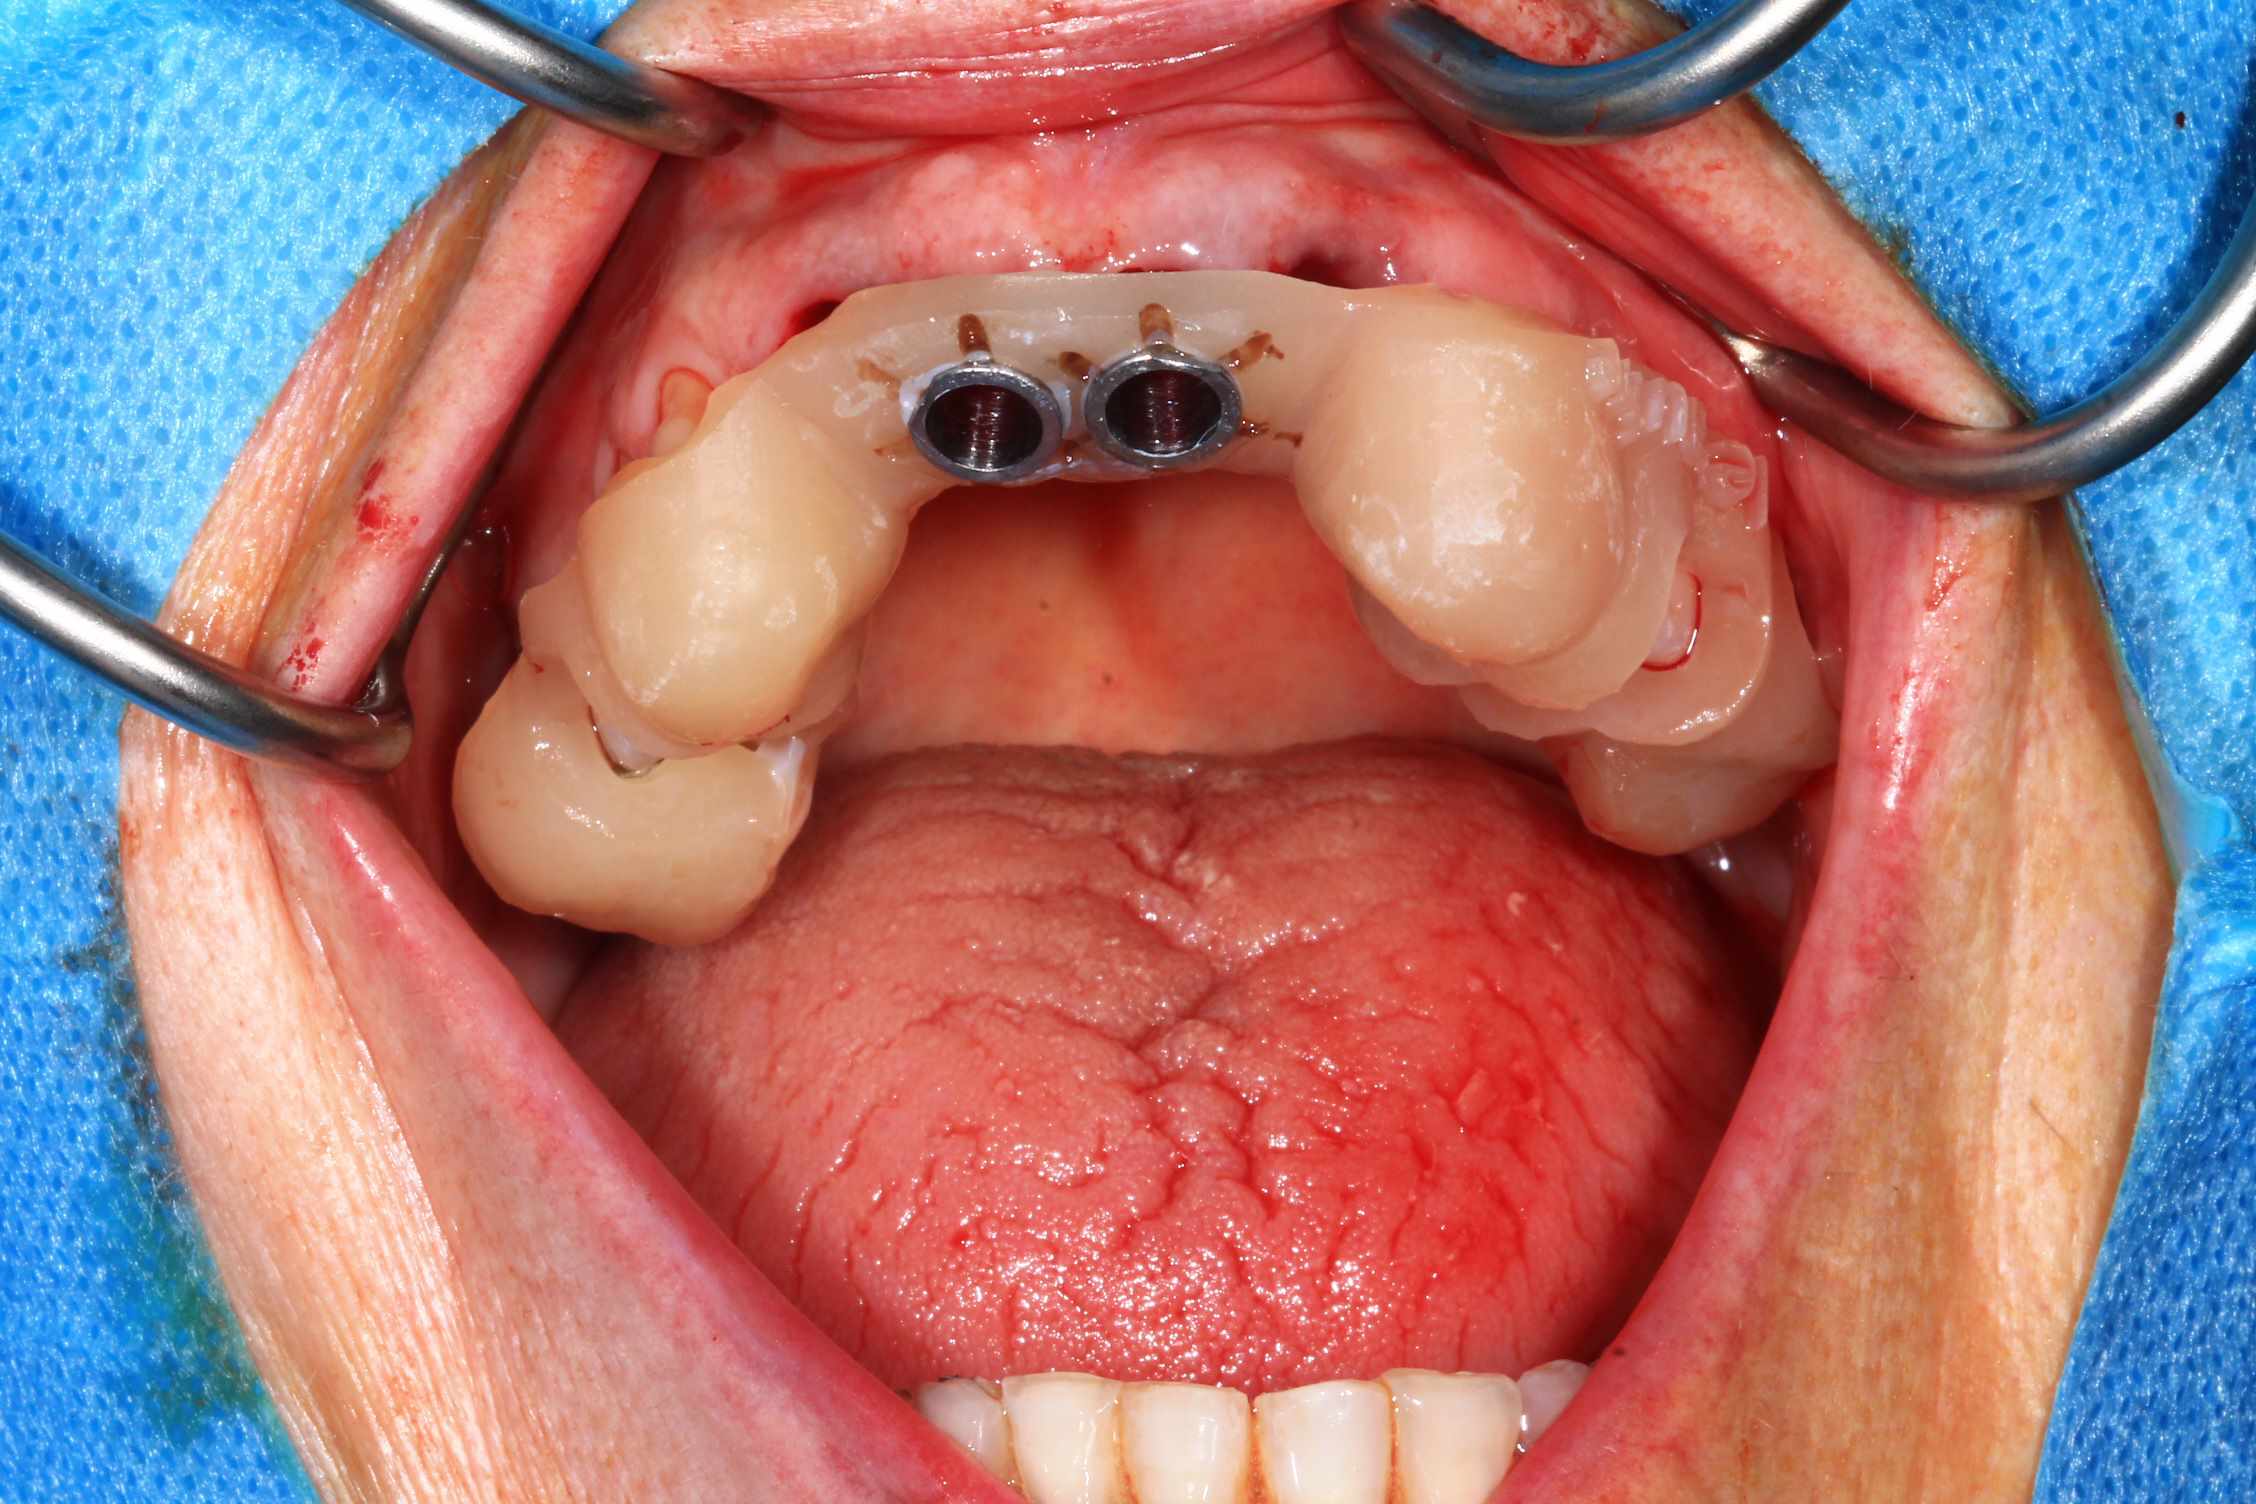

Chir : extraction, implant flapless et pose du bridge imprimé Flexera rosenscrew.

3 h de planif, modélisation du guide, puis 2 h environ pour la simulation de la chir , le modelisation et l'impression du bridge, qui tombe pile, zero retouche occlusale.

simulation de la chir. scan, matching des elements avec medit design, finition du bridge dana meshmixer.